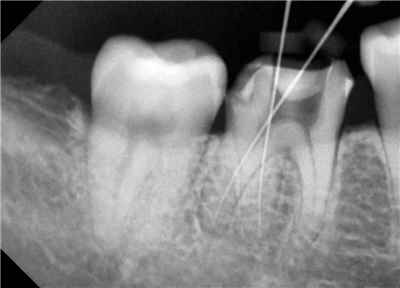

치아 단면. 노란색은 치아 표면, 파란색은 법랑질, 빨간색은 상아질. 법랑질에는 미세 공극이 있고, 상아질에는 치수와 연결되는 상아세관이 있습니다. (출처: SPL / Barcroft Media)